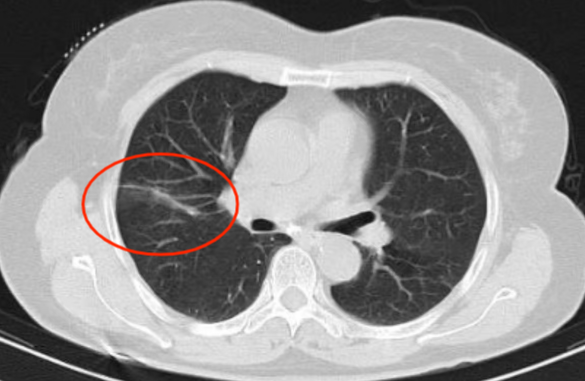

近年来,贵州航天医院各科室紧跟医学前沿,不断强技术、补短板,大力开展新技术、新项目,完成了许多高精尖、高难度、本地区“首例”的技术,填补了医院医疗技术空白,满足了群众日益增长的医疗需求。 贵州航天医院呼吸与危重症医学科是贵州省内呼吸疾病治疗规模最大,诊疗项目最全的呼吸疾病品牌科室,呼吸介入技术达到了全国先进水平,在贵州省内处于领先的地位。 本期,我们将为大家带来呼吸与危重症医学科特色技术——氩氦刀冷冻消融技术治疗肺癌、高危肺结节。 案例分享 患者在体检时发现右肺结节(10mm),就诊于当地我院一专科联盟合作医院,但因当地医疗条件有限,患者通过专科联盟绿色通道前往我院就诊,入院后,通过经皮肺穿刺活检,病理诊断为右肺原位腺癌,科室立即组织专家开展肺结节多学科会诊(MDT),为患者制定诊疗方案。 经充分的沟通下,患者及家属拒绝手术切除。科室再次严格讨论评估,患者情况满足氩氦刀冷冻消融术指征,再次将治疗方案与患者及家属沟通同意后,为患者制定并成功实施氩氦刀冷冻消融术。 冷冻消融术中 术后,患者定期复查,恢复效果良好。 术前 术后即刻 术后1月(反应性增大) 术后6月(纤维条索) 术后12月(纤维条索变细) 什么是氩氦刀冷冻消融技术 氩氦刀冷冻消融技术是一种先进的微创超低温冷冻消融肿瘤的医疗技术,它利用氩气和氦气的快速温度变化特性,实现对病变组织的精准冷冻和复温,以达到消融和破坏肿瘤细胞的目的。 氩氦刀冷冻消融技术原理 氩氦刀冷冻消融技术基于焦耳-汤姆逊效应,通过氩气和氦气的快速交换实现局部组织的超低温冷冻(-140℃到-190℃)和快速复温(20℃到45℃),当氩气通过金属杆尖端的蒸发器时,其气压突然降低,会大量吸收周围的热量,使金属杆尖部的气温迅速下降到超低温;随后,氦气在极短的时间内使组织迅速复温,通过热胀冷缩的原理,使肿瘤细胞爆裂。 (一)直接杀伤( 靶区冷冻消融效应) 1.快速冷冻(降温段):细胞内冰晶快速生长并撕裂细胞,导致细胞损坏。 2.慢速冷冻(低温段):细胞外冰晶生长导致水渗出细胞,造成细胞脱水。 3.升温:水迅速进入细胞,导致细胞涨破。 (二)间接杀伤( 冷冻的血管栓塞效应) 病灶区域快速冷热交替,引起微血管细胞脱水、蛋白质变性、微血管损伤、 冰晶及微血栓在微血管内形成,导致血小板聚集、血管栓塞, 局部细胞缺血坏死。 (三)抗肿瘤免疫( 冷冻免疫激活效应) 随着肿瘤细胞的破裂和坏死,促使肿瘤免疫调节因子停止分泌,逆转免疫抑制状态;可调控表面抗原,促进淋巴细胞增殖,提高身体抗肿瘤免疫能力。 氩氦刀冷冻消融技术优势 (一)精准度高:通过精确的靶点定位和温控技术,可实现对病变组织的精准冷冻和复温,避免损伤正常组织。 (二)微创治疗:对周围正常组织的热损伤小,无需开胸开腹,仅有一个针孔,恢复快,几乎无疤痕。 (三)适应症广:肺腺体前驱病变(癌前病变)、甲状腺结节、乳腺结节等;多原发磨玻璃肺结节,因各种原因不适合手术的早期肺癌、肝癌等;内科治疗无法控制的少发转移瘤等。 (四)可重复治疗:由于冷冻治疗对身体的创伤和痛苦较小,可以多次重复进行治疗,这对巨大的肿瘤和多发的肿瘤尤其适用。 (五)无毒性:冷冻治疗是以物理方法杀灭肿瘤,不向体内注射任何药物,避免外科手术、化放疗等对身体带来的巨大创伤和毒副作用,能有效减轻患者肿瘤负荷和痛苦,因此与化放疗、分子靶向药物等治疗方式相比属于无毒治疗。 氩氦刀冷冻消融技术对于早期肺癌、高危结节,可作为手术的替代治疗。对于晚期较大的肿瘤可作为姑息治疗,增强综合治疗的效果,可减少肿瘤负荷,减轻症状,提高生活质量,延长生存时间。 近年来,随着医学影像技术发展和肺癌筛查的广泛开展,肺内结节的检出率显著提高。无论肺内磨玻璃结节还是实性结节,单发或多发,都需要引起重视,定期复查,动态观察结节变化,如有需要请积极治疗。 贵州航天医院 呼吸与危重症医学科专家团队 廖江荣 国务院政府特殊津贴专家、遵义市呼吸疾病临床医学中心学科带头人、二级教授、主任医师 学术任职: 亚洲冷冻治疗学会副主席 第二届中国医药教育协会介入微创专业委员会呼吸分会副主任委员 中国抗癌协会肿瘤微创治疗专业委员会常务委员 中国防痨协会结核病转化医学专业分会常务委员 第一届中国人体健康科技促进会呼吸介入专委会常务委员 中国医疗保健国际交流促进会结核病学分会第三届委员会常务委员 中国抗癌协会肿瘤微创治疗专业委员会粒子治疗学组第四届委员会委员 中国结核病防治综合质量控制专家指导委员会委员 “西部呼吸介入联盟”副理事长 专业擅长: 呼吸系统(肺)疑难病的诊断及危重病的抢救,呼吸系统(肺)感染性、疑难性疾病介入快速诊断(ROSE),尤其在肺癌、肺小结节早期诊断,肺癌微创综合靶向治疗,难治性、复治性、重症肺结核诊疗,硬质支气管下复杂性气道狭窄诊治,纤支镜介入治疗气道肿瘤、结核、气道狭窄(球囊扩张、支架植入、高频电刀、氩气刀、冷冻、灌洗、注药、微波消融),间质性肺疾病的诊疗上具有极高水平;带领团队勇于创新,在贵州省率先开展多项新技术、新疗法,如CT引导下及纤支镜下I125粒子植入及CT引导下微波、冷冻消融介入治疗肺癌等多项新技术,带动了贵州省肺部疾病的介入治疗水平提高。 唐永江 四川大学华西医院 呼吸与危重症医学科 副主任医师 呼吸危重症医疗组长 香港中文大学博士 美国康奈尔大学访问学者 贵州航天医院 呼吸与危重症医学科 学科带头人 主要从事呼吸危重症(特别是呼吸重症感染)的临床及科研工作。 PCCM专培结业医师 中华医学会呼吸病学分会呼吸危重症学组秘书 中华医学会呼吸病学分会ECMO工作组成员 四川省医学会呼吸病学专委会介入学组委员兼秘书 发表文章20余篇,主持及参与多项国家自然科学基金及省卫健委基金。 蒋 婷 呼吸、感染党支部书记,呼吸与危重症医学科主任,副主任医师 专业擅长:从医20余年,在呼吸系统疾病、介入呼吸病学、肺部结核、肺部肿瘤等方面具有丰富的临床经验和专业技能,尤其是慢性阻塞性肺疾病、支气管扩张、肺结核、耐药肺结核、肺癌、胸腔积液等肺部疾病的诊治、微创介入、危重病患者抢救。 现任中国防痨协会人兽共患结核病专业分会委员,中国女医师协会第一届介入专业委员会委员,贵州省基层呼吸疾病防治联盟-间质性肺疾病联盟委员,贵州省防痨协会第七届理事会理事,贵州省中西医结合学会呼吸专业委员介入呼吸病学组委员,贵州省遵义市中医药学会中西医结合肺病(呼吸)分会副主任委员,贵州省遵义市中医药学会中医肿瘤专业委员会常委;发表论文数篇,参与并主持多项科研项目。 王 云 中共党员,呼吸与危重症医学科一病区副主任,副主任医师 专业擅长:擅长呼吸系统常见病及疑难危重症、介入呼吸病学、肺部肿瘤疾病的诊治,尤其擅长快速现场评价(ROSE)技术。 贵州省中西医结合学会呼吸专业委员会介入呼吸病学组委员,遵义市中医药学会中西医结合肺病(呼吸)分会委员,贵州省中西医结合学会第六届呼吸专业委员会委员。 李桂凤 中共党员,呼吸与危重症医学科三病区主任,副主任医师 专业擅长:从事呼吸系统疾病、结核病学、介入呼吸病学、肿瘤综合治疗、呼吸康复等临床工作20余年,擅长呼吸内科常见病、多发病及疑难重症危重病症的诊治,尤其对重症疑难结核及耐药结核病、介入治疗(肺)呼吸系统疾病、呼吸危重病抢救等方面具有较高诊疗水平。 中国防痨协会非结核病专业委员会委员,贵州省中西医结合学会第六届呼吸专业委员会委员,贵州省康复学会睡眠障碍康复专业委员会委员,遵义市呼吸内科医疗质量控制中心委员,遵义市落实民生实事结核病筛查阅片专家组成员;主持及参与实用新型专利3项。 周裕祥 中共党员,呼吸与危重症医学科四病区主任,副主任医师 专业擅长:经皮肺介入、经血管介入诊疗技术。 贵州省中西医结合学会呼吸专业委员会介入呼吸病学组常务委员,中国医师协会呼吸医师分会介入呼吸病学工作委员会呼吸病血管介入学组委员,贵州省中西医结合学会呼吸学分会委员,遵义市医学会放射肿瘤治疗学分会委员,中国医药教育协会介入微创呼吸分会委员,北京健康促进会中青年专家委员会胸部疾病精准活检分委会委员;曾赴重庆医科大学RICU、珠海市人民医院介入科进修学习。 杨 芳 中共党员,呼吸与危重症医学科内镜中心主任,副主任医师 专业擅长:从事临床工作约20年,对呼吸危重病的救治有独到的见解,尤其擅长呼吸系统疾病的介入诊疗,对呼吸内镜下的诊治及经皮肺穿刺诊疗技术具有丰富的临床经验。 亚洲冷冻治疗学会委员,中国医药教育协会介入微创呼吸分会委员,西南结核病医院联盟第二届委员会秘书/委员,贵州省中西医结合学会第六届呼吸科专业委员会委员,贵州省中西医结合学会呼吸专业委员会介入呼吸病学组秘书,贵州省中西医结合学会呼吸专业委员会基层康复学组副组长,贵州水利电力医学科学技术会高原医学分会委员,遵义市中医院学会中西医结合肺病(呼吸)分会秘书/常务委员,遵义市医学会肿瘤学分会(第二届)委员,遵义市医学会放射肿瘤治疗学分会第二届委员;主持及参与科研课题多项,参编著作《呼吸内镜操作技术规范》、《介入结核病学》,发表论文数篇。 贵州航天医院 呼吸与危重症医学科简介 贵州航天医院呼吸与危重症医学科以呼吸危重症和介入呼吸病学为强力推手,以肺部感染性疾病及肺癌、肺小结节的早期精准诊疗、慢性呼吸疾病康复治疗为特色,以人才团队建设为核心的科室发展模式,现已成为贵州省内呼吸疾病治疗规模最大、诊疗项目最全的呼吸疾病品牌科室。是贵州省医学重点学科、临床医学重点专科建设单位,遵义市首批呼吸重点学科、重点专科建设单位。是国家卫健委能力建设和继续教育肿瘤微创介入建设中心、贵州省县级医院微创介入培训中心、遵义市呼吸疾病临床医学中心。是国家呼吸医疗质量控制与管理哨点医院、遵义市呼吸内科专业医疗质量控制中心。是中国医药教育协会介入微创呼吸分会呼吸介入技术培训中心单位;国家卫健委海医会呼吸分会ROSE专委会“诊断性介入肺脏病学快速现场评价”培训基地;中国肺癌防治联盟“贵州航天医院肺结节诊治”分中心,中国人体健康科技促进会呼吸介入技术培训基地,贵州省中西医结合会呼吸学分会呼吸介入专委会主委单位。 基本情况 平均每年开展气管镜诊疗约4000例,经皮肺穿刺介入诊疗近千例,开展的项目包括经支气管镜(软、硬)下冷冻、氩气刀、高频电刀、球囊扩张、支架置入、超声内镜诊疗等气道介入诊疗技术,经皮肺穿刺活检及肿瘤消融术(微波、冷冻)、ROSE技术、内科胸腔镜诊疗及经血管介入诊疗技术,且多项呼吸介入诊疗技术在省内处于领先水平。 诊疗范围 专科擅长:致力于呼吸系统感染性、疑难性疾病的介入快速精准诊疗;肺癌与肺小结节早期精准诊疗水平项目提升。擅长呼吸系统(肺)疑难病的诊断及危重病的救治,尤其是肺癌、肺小结节的早期诊断,肺癌综合靶向治疗,肺结核综合诊疗等肺部疾病的介入诊疗在贵州省内处于前沿水平。 肺结节MDT门诊 贵州航天医院呼吸与危重症医学科微创介入诊疗技术已达到国内前列,省内领先水平,是亚洲冷冻治疗学会常务理事单位,并获批成立遵义市肺结节多学科(MDT)微创诊疗中心。 出诊信息 出诊时间: 周一至周五 8:00--12:00;14:00--17:00 出诊地点: 遵义市肺结节多学科微创诊疗中心(MDT)门诊(贵州航天医院呼吸综合楼1楼) 呼吸与危重症医学科与心胸外科、医学影像科、麻醉科等科室建立了多学科(MDT)会诊机制,结合患者情况,通过采取外科手术、冷、热消融等多种治疗手段,帮助患者安全、有效、精准、科学、快速治疗肺结节,单次消融手术时间约半小时左右,几乎没有疼痛,且并发症少,3-5天即可出院,有效减少了患者因开刀手术需长时间恢复的痛苦。 一审一校:周裕祥、黄成成